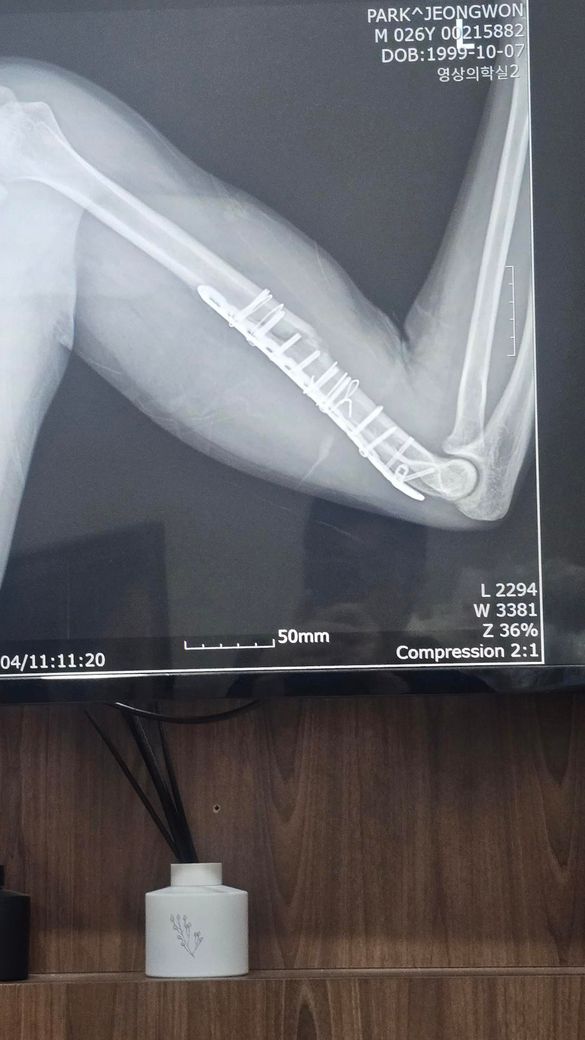

현재 골절 수술후 106일차에요.. 8도정도 틀어졌고 정복이 잘 안됐다고 하는데 아직은 기다려볼 단계일까요 진료는 여러군데 더 예약해놨어요.. 수술부위는 좌우 움직일 때 뼈소리 자주나요

엑스레이상 상완골 원위부의 분쇄골절로 인해 정복이 완벽하지 않고, 금속판 주위로 일부 각변형이 관찰되는 상태입니다.

수술 후 100일이 넘은 시점에서 골절선이 여전히 뚜렷하게 보이며 빈 공간을 채우는 뚜렷한 골진형성이 다소 더뎌 보여 부정유합이나 불유합의 가능성을 염두에 두어야 하는 시기인것은 맞습니다. 다만 부정유합은 뼈가 아예 붙지 않는것이 아니라 잘못된 모양으로 붙는것을 의미하며, 현재의 각도가 기능에 큰 지장을 주지 않는다면 무조건적인 재수술보다는 경과를 더 지켜볼수도 있습니다. 움직일때 나는 소리는 골절부위의 미세한 움직이미 때문일수 있으므로 절대적인 안정과 추가적인 고정이 필요할수 있습니다. 예약된 진료를 통해 골유합진행 여부를 면밀히 확인하시길 권합니다. 빠른쾌유를 빕니다!

• 제시된 영상은 상완골 간부 골절에 대해 금속판 고정술 시행 후 약 3개월 경과한 상태로 보이며, 골절 부위의 정렬은 유지되고 있으나 피질 연속성이 완전히 회복되었다고 보기는 어렵고 가교성 골진 형성도 충분히 성숙한 형태로 뚜렷하게 보이지는 않습니다. 초기 전위가 있었고 현재 약 8도 정도의 각형성이 남아 있는 점을 고려하면, 현재 단계에서 가장 우선적으로 의심되는 것은 부정유합이라기보다는 지연유합입니다.

상완골 간부 골절은 다른 장관골에 비해 유합이 늦는 경우가 흔하며, 수술 후 3개월 시점에서는 유합이 진행 중일 수 있는 시기입니다. 다만 이 시기에 골진 형성이 부족하거나 골절선이 여전히 명확하게 남아 있다면 향후 유합 지연 또는 불유합으로 진행할 가능성이 있어 주의가 필요합니다. 8도 정도의 각형성은 기능적으로 허용 범위에 속하는 경우가 많으나, 회전 변형이나 통증, 기능 제한이 동반되면 임상적 문제로 이어질 수 있습니다.

움직일 때 느껴지는 소리는 단순 연부조직 마찰일 수도 있으나, 골절 부위의 미세한 움직임이나 고정 안정성 부족을 시사하는 경우도 있어 경과 관찰에서 중요한 단서가 됩니다. 특히 통증이 지속되거나 점차 증가하는 양상이면 유합 지연 또는 고정 실패 가능성을 더 신중하게 봐야 합니다.

현재 시점에서는 즉시 재수술을 결정하기보다는 유합 진행 여부를 객관적으로 평가하는 것이 중요하며, 단순 방사선 외에 CT를 통해 골절면의 실제 연결 여부를 확인하는 것이 도움이 됩니다. 일반적으로 수술 후 3개월에서 6개월 사이에 유합이 진행되지 않거나 정체되는 경우, 또는 통증과 기능 저하가 지속되는 경우에 재수술을 고려하게 되므로, 현재는 다기관 진료를 통한 2차 의견과 함께 일정 기간 추적 관찰을 병행하는 접근이 타당한 단계로 판단됩니다.